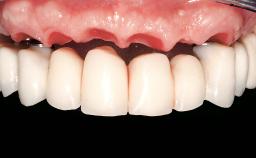

Immediate Loading of Six Implants in the Maxilla and Final Restoration with a Full-Arch Gold/Ceramic FDP Involving the Concept of Tilted Implants

A 61-year-old male patient with a failing fixed maxillary rehabilitation and a fixed mandibular rehabilitation requested a new fixed maxillary rehabilitation. The patient was wearing a temporary metal-reinforced maxillary bridge inserted two years before the consultation. He reported that his previous dentist did not want to insert a definitive framework because he considered the residual teeth to have a negative prognosis. The patient reported a history of recurrent caries and endodontic complications as the main reason for the previous extractions. The anamnesis was negative for periodontal disease and bruxism. The patient’s chief compliant was the mobility of his maxillary prosthesis, which needed to be re-cemented frequently, and discomfort during chewing.Moreover, the patient was not satisfied with the esthetic appearance of his maxillary teeth, which he found too long. The patient asked for a stable and comfortable fixed maxillary rehabilitation and firmly rejected any removable solution.

Prosthesis Type FDP

Patient's Esthetic Expectations Low Medium High

Esthetic Risk Medium